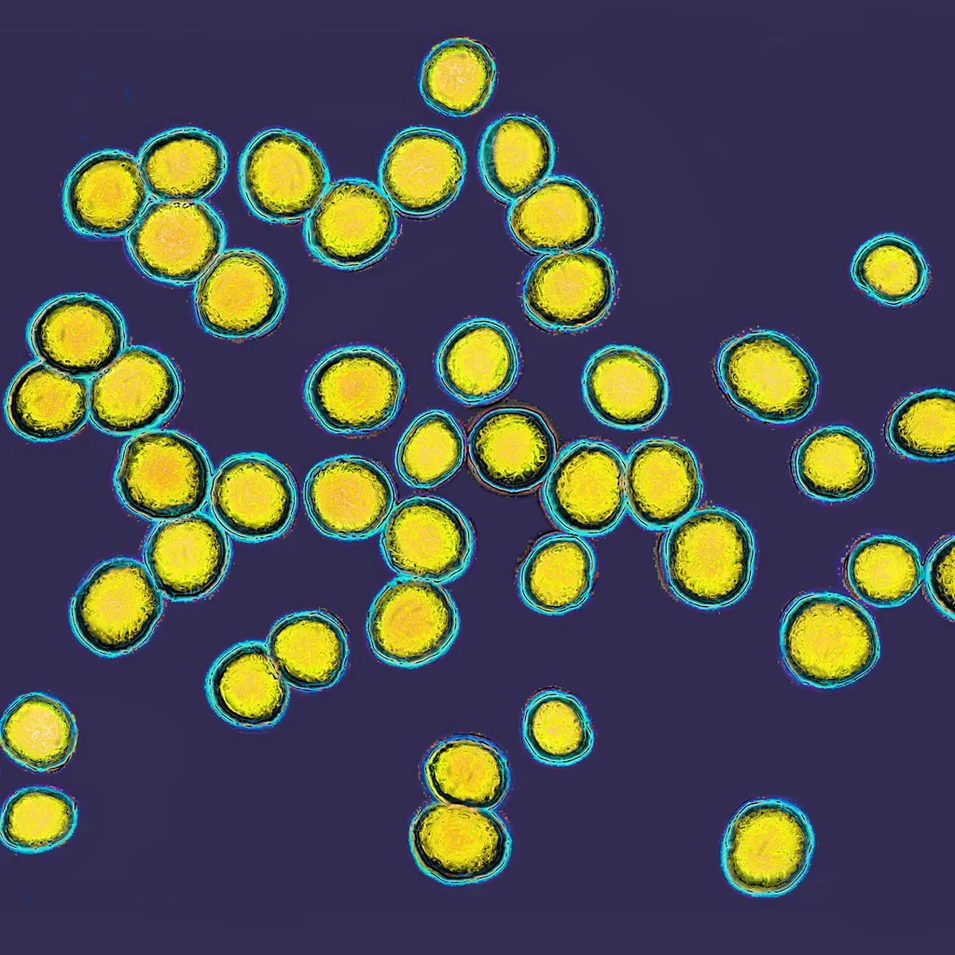

Ova istraživanja se oslanjaju na otkriće da kožu ljudi koji pate od ekcema uglavnom naseljava Staphylococcus aureus (zlatni stafilokok), bakterija koja često ima patogena svojstva.

„Jedan od najvećih problema kod bolesti poput ekcema je što određene patogene bakterije, kao što je Staphylococcus aureus, naseljavaju površinu kože i izazivaju osip, bolesti i infekcije”, kaže Galo, čiji tim već godinama istražuje načine na koje bi mikrobiom kože mogao da se iskoristi za suzbijanje štetnih bakterija kod pacijenata koji pate od ekcema.

Galo i njegov tim usredsređeni su na Staphylococcus hominis, bakteriju koja je prirodno prisutna na koži i koju ima oko 21 odsto zdravih ljudi, ali samo jedan odsto onih koji pate od atopijskog dermatitisa.

„Naša koža pruža komenzalnim (korisnim) bakterijama poput Staphylococcus hominis bezbedno mesto za život, pa su neke od njih razvile način da štite svoju sredinu od štetnih bakterija koje pokušavaju da napadnu”, objašnjava Galo.

Bakterija Staphylococcus hominis proizvodi antimikrobne (odbrambene) peptide, male delove proteina koji direktno ubijaju Staphylococcus aureus.

Takođe proizvodi hemijske supstance koje onemogućavaju bakterijama da međusobno komuniciraju.

Neke bakterije, kao što je Staphylococcus aureus, međusobno „komuniciraju” kada njihova populacija dostigne određenu gustinu.

Ovaj mehanizam poznat je kao quorum sensing (način komunikacije između bakterija iste ili različite vrste posredstvom signalnih molekula) i pokreće lučenje toksina koji mogu da izazovu upale kože.

Onemogućavanjem te komunikacije može da se spreči oslobađanje toksina.

Galoov tim je 2021. godine sproveo randomizovano kontrolisano ispitivanje prve faze, tokom kojeg je 54 odraslih koji pate od atopijskog dermatitis nedelju dana nanosilo kremu koja je sadržala žive bakterije Staphylococcus hominis.

Rezultati su pokazali da je tretman ovom bakterijom značajno smanjio prisustvo Staphylococcus aureus na koži, a kod podgrupe pacijenata smanjeni su crvenilo i svrab koji prate atopijski dermatitis, u poređenju sa kontrolnom grupom koja je koristila placebo kremu.